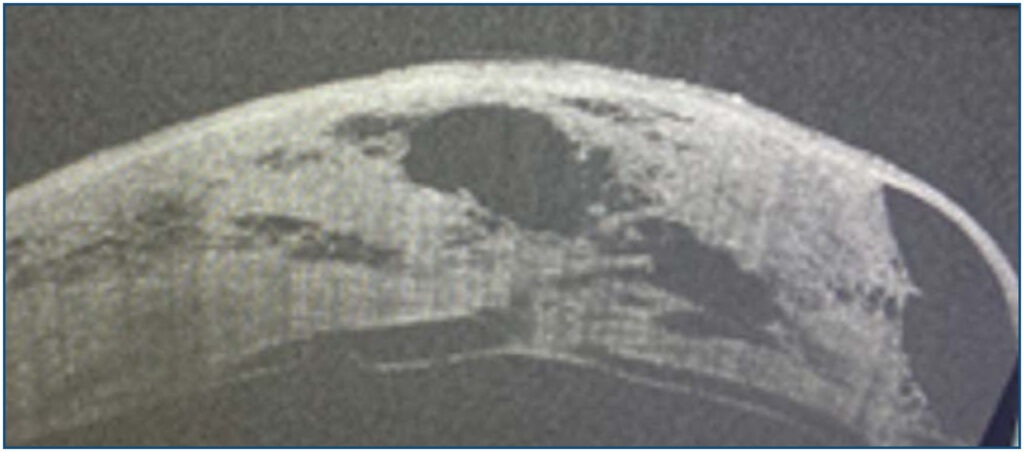

Use of autologous intrastromal blood in ocular perforation after hydrops

A 46-year-old male who was already diagnosed with keratoconus presented with hydrops followed by a small corneal perforation. At first, the perforation was managed with a cyanoacrylate glue and therapeutic contact lens; however, the advanced keratoconus did not allow stabilization of the contact lens, and the patient developed intense pain, making it impossible to maintain the cyanoacrylate glue. An intrastromal injection of autologous blood was then performed at the operating room, which was effective in containing the perforation. After the hydrops condition improved, the patient underwent penetrating corneal transplantation for visual rehabilitation.